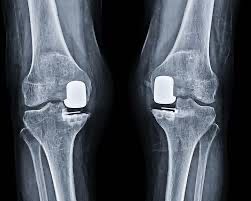

Dr. Manal Gore is a highly skilled Consultant Orthopaedic Surgeon specializing in the diagnosis and treatment of musculoskeletal disorders. With expertise in Robotic & Conventional Joint Replacement, Complex Trauma Surgery, Arthroscopy & Sports Medicine, Minimally Invasive Procedures, and Osteoarticular Infection Management, Dr. Gore provides comprehensive orthopaedic care for patients of all ages.

With a strong focus on evidence-based medicine, Dr. Gore is committed to delivering personalized treatment plans that ensure faster recovery, improved mobility, and long-term outcomes. His clinical approach combines advanced surgical techniques with non-surgical care, helping patients return safely to their daily activities, sports, and pain-free movement with confidence.